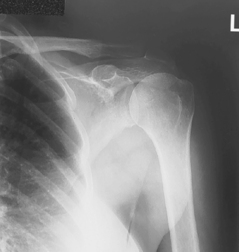

Posterior oblique (Grashey method) (S)

Posterior oblique (Grashey method) critique